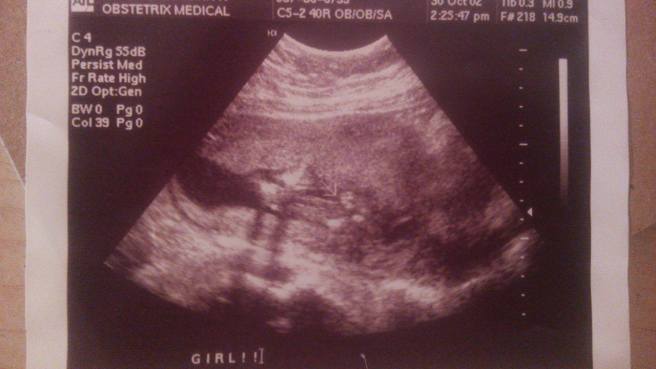

So the day I found out what I was having finally came. As I laid on the table with my belly exposed, there was a part of me that wished I wasn’t alone. I wanted to share this experience with someone. I wanted someone to be just as excited as I was. I wanted someone to hold my hand and tell me it was all going to be okay. The sonographer squirted some of that jelly out on my stomach and placed the ultrasound instrument on my belly. First she was going to take a look at the baby’s spine. Everything looked fine from the angle she saw, but she cautiously advised me that it did not completely rule out spina bifida. She then began looking at the size of the baby. She said the baby was growing well and was at a good, healthy weight. I exhaled in relief. Any sign of a healthy baby, I grabbed a hold of. Good heart rate. I’ll take it. Baby is moving. Another one. No complications. Cross my fingers that it will last. She then asked if I would like to find out the sex of the baby. Of course! Up till now the baby stuff I had bought consisted of greens and yellows. I was excited to start buying a lot of blue or a lot pink. She placed the instrument below my belly button, using a slight amount of pressure. She moved it back and forth until she got the image that she wanted. Ok, Christin…it looks like you are having a GIRL! All at once an emotion that I had never experienced before hit me. I was going to have a daughter. A tear or two slipped out the corner of eyes. A daughter. I was going to have a precious baby girl. Birth defect or not, I was going to be the best mom I could be. No matter what disabilities she could be born with, physical, developmental or both—I was going to be the best mom to her. I would figure it out. At this point, nothing else mattered.